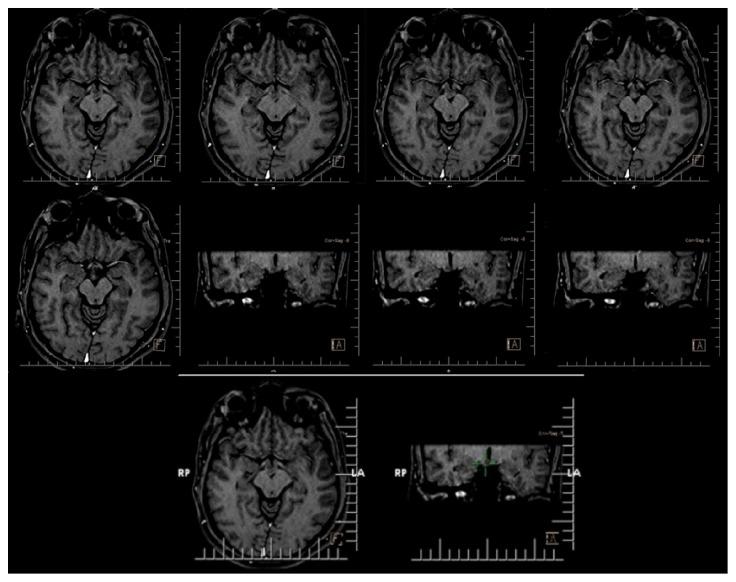

. Hypothalamic hamartomas (HHs) are rare tumor-like malformations that may present with complex partial seizures refractory to anticonvulsants in adulthood. The condition may be misdiagnosed because of rarity. . We report a 25-year-old man with complaint of seizures presented by falling, tonic spasm of limbs, oral automatism, vocalization, and hypermotor activities. His seizures started at the age of one month and presented as eye deviation and upper limbs myoclonic jerk, followed by frequent seizures with variable frequency. The patient had delayed developmental milestones and was mentally retarded. He was hospitalized and underwent video-EEG monitoring and neuroimaging, and the diagnosis of HH was made. The patient became candidate for surgery after that. . In this case, the underlying etiology of seizures was diagnosed after 25 years. HH is a rare condition and neurologists may encounter very small number of these cases during their practice. Therefore, they should consider it in patients who present with suspected signs and symptoms.

下丘脑错构瘤(HHs)是一种罕见的肿瘤样畸形,在成年期可能表现为对抗惊厥药难治的复杂部分性癫痫发作。由于其罕见性,这种疾病可能会被误诊。我们报告一名25岁男性,主诉有跌倒发作、肢体强直性痉挛、口部自动症、发声及多动等癫痫症状。他的癫痫发作始于1个月大时,表现为眼球偏斜和上肢肌阵挛性抽搐,随后发作频率不一且频繁发作。该患者发育里程碑延迟且智力发育迟缓。他住院并接受了视频脑电图监测和神经影像学检查,最终确诊为HH。此后该患者成为手术候选对象。在这个病例中,癫痫的潜在病因在25年后才得以诊断。HH是一种罕见疾病,神经科医生在其临床实践中可能仅会遇到极少数此类病例。因此,对于出现可疑症状和体征的患者,他们应考虑到这种疾病。